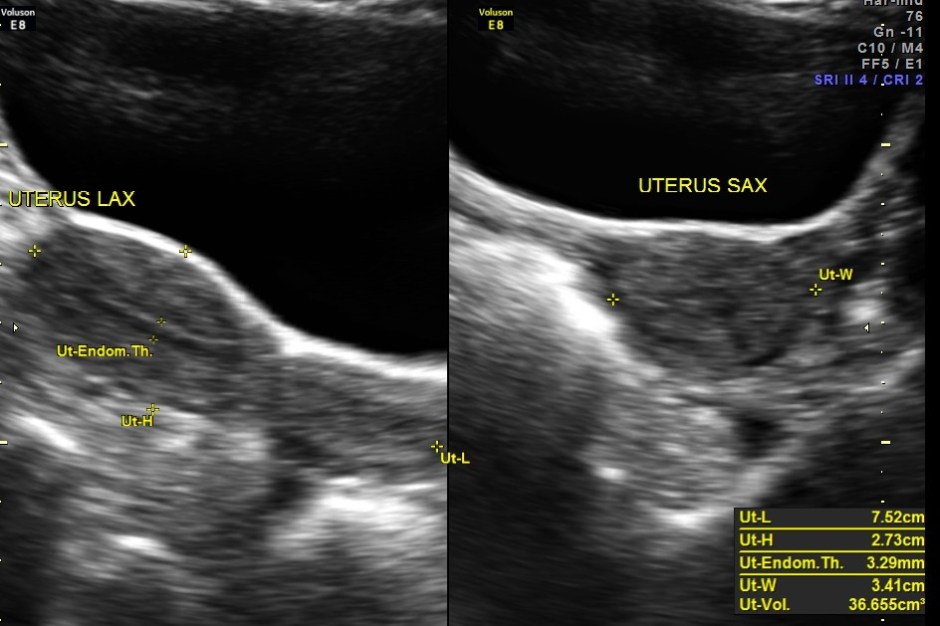

Ultrasound revealed normal liver, gall bladder, pancreas, spleen ,post menopausal shrunk uterus and normal right kidney.